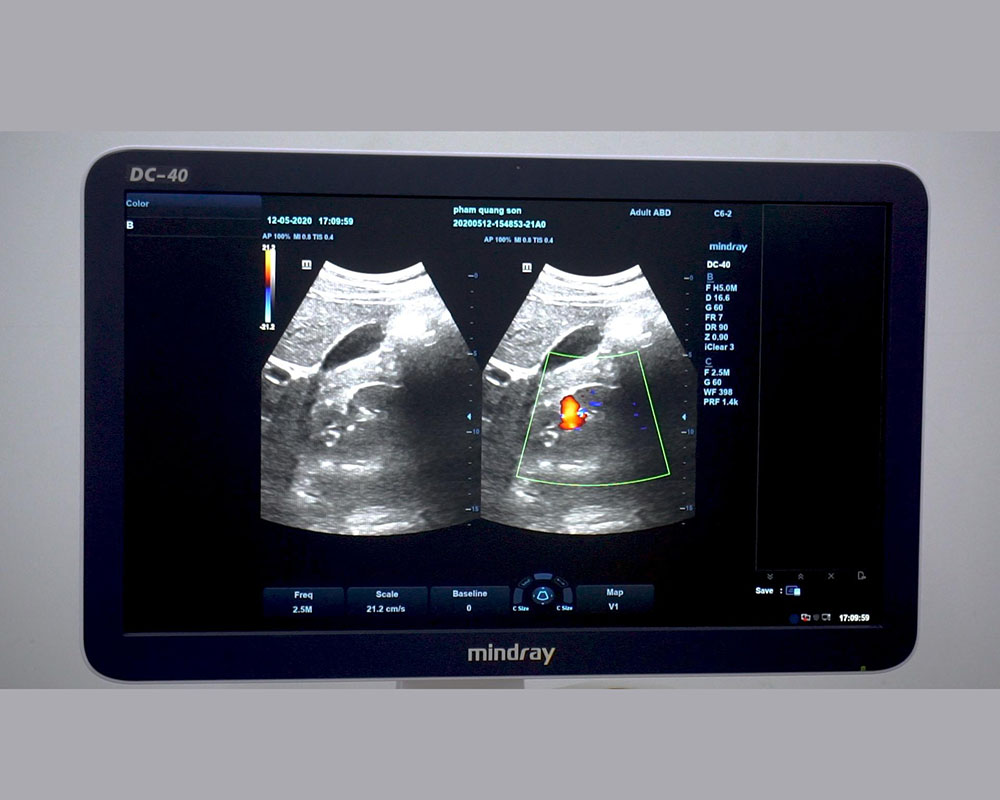

Hình ảnh Doppler trên đầu dò Convex C6-2